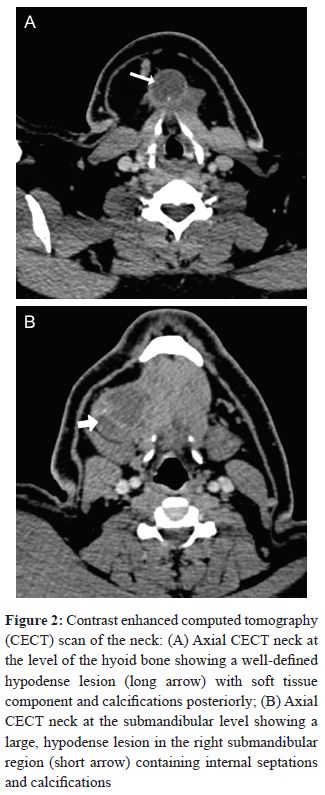

Neck USG showed a well-defined hypoechoiccystic lesion measuring 3 × 3 × 5 cm in diameter in the submental region and another lesion in the right submandibular region. There was a prominent soft tissue component with calcifications noted within the lesion (Figure 1).

The thyroid gland was normal in appearance; bilateral cervical lymphadenopathy, mostly at level II and III, was also seen. A CT scan of the neck with intravenous contrast administration showed a midline complex cystic mass with peripheral enhancing walls, thick internal septations, and an enhancing soft tissue component along with coarse calcifications at the hyoid bone level (Figure 2).